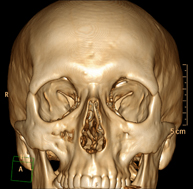

- TC Macizo facial

Prueba radiológica que consiste en obtener imágenes del macizo facial (cara) de alta definición anatómica mediante el empleo de un equipo de TC (Tomografía Computarizada). Indicaciones: tumores, cirugía plástica.